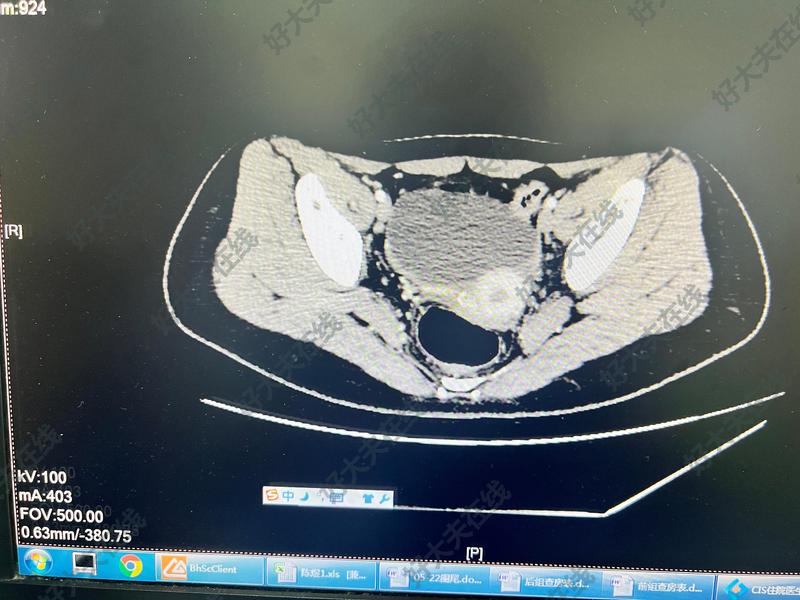

治療前運動后反復腹痛,CT檢查發(fā)現(xiàn)盆腔囊腫,大小約9×8×7cm治療中完善檢查后行腹腔鏡探查,采用兩部位方法,術(shù)中發(fā)現(xiàn)囊腫為右側(cè)輸卵管系膜來源,大小約9×8×8cm,內(nèi)含透明液體,遠端緊貼卵巢,術(shù)中予以完整剝離,創(chuàng)面予以倒刺線縫合關(guān)閉。治療后治療后即刻術(shù)中完整剝離囊腫,腹壁傷口美觀,創(chuàng)口小。